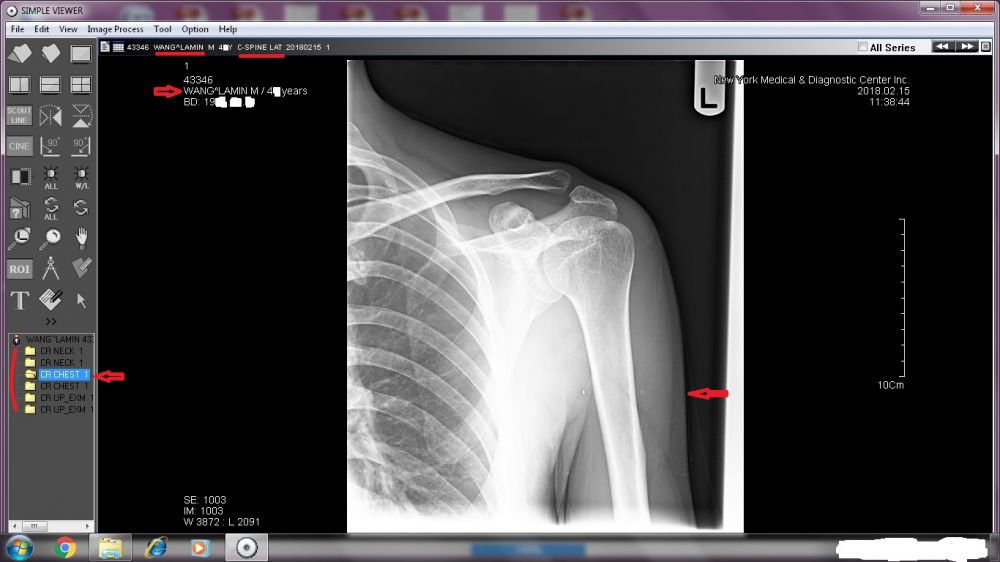

A TREMENDOUS amount needs to be revealed. Right now, I will start with the two sets of X-ray images done by New York Medical & Diagnostic Center (80-46 Kew Gardens Rd, Kew Garden, NY 11415. Tel: (718) 261-1000 ).